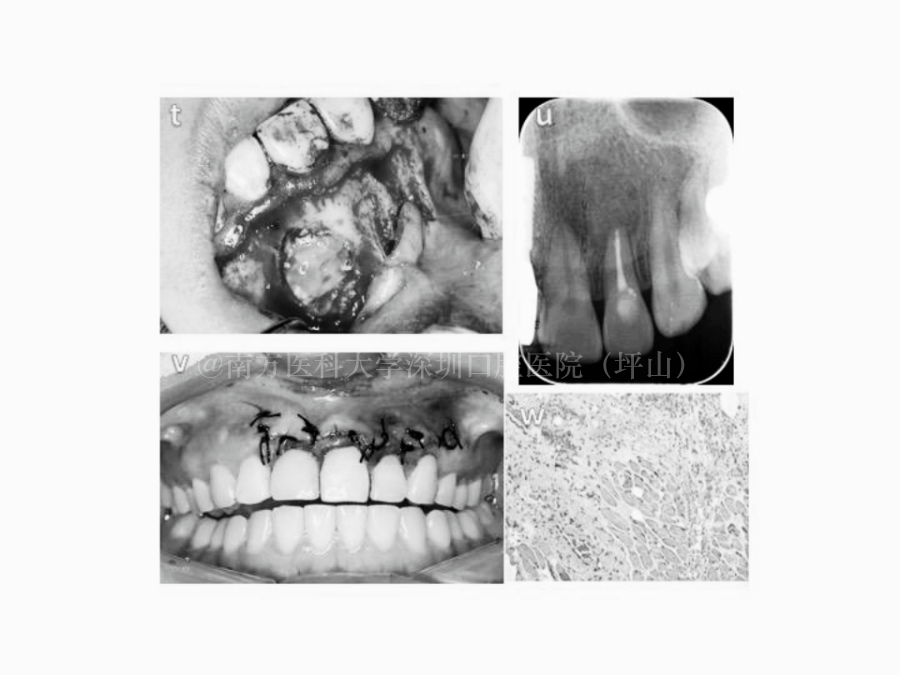

根尖外科手术案例

根尖外科手术

这颗牙的根尖出现了很大的阴影,表明存在大面积的病变,但是她的牙齿里面根管的通路被堵上了,所以治疗很困难。

医生通过显微根管治疗成功打通根管,又通过手术把根尖区的囊肿摘除掉,慢慢恢复。通过根管治疗和根尖外科手术,既实现了保留牙齿的目的,又清除了病变。

成釉细胞瘤